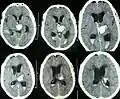

- Hémorragie cérébrale : la principale manifestation clinique de l'angiopathie amyloïde est l'hémorragie intracérébrale de topographie lobaire ou cérébelleuse[7]. La topographie lobaire regroupe les structures corticales et sous-corticale (c'est-à-dire proche de la surface du cerveau). Elle est principalement définie par opposition à la topographie profonde qui englobe essentiellement les ganglions de la base (en particulier le thalamus ou le noyau lenticulaire) et le pont. Cette distinction topographique est importante dans la mesure où l'hémorragie cérébrale lobaire est très évocatrice d'AAC alors que l'hémorragie cérébrale profonde est plutôt évocatrice de microangiopathie hypertensive. Cette distribution reflète l'atteinte préférentielle des petits vaisseaux corticaux dans l'AAC et de artères lenticulo-striées dans l'angiopathie hypertensive[8]. Cependant, parmi l'ensemble des topographies lobaires possibles, l'atteinte du lobe temporal ou occipital semble prédominante, en particulier si le patient avait déjà présenté une hémorragie dans ces régions[9]. Comme pour l'ensemble des AVC, les symptômes associés aux hémorragies cérébrales de l'AAC sont variables. Ils dépendent avant tout de la taille de l'hémorragie et de sa localisation.

Scanner cérébral objectivant une hémorragie lobaire temporale droite évocatrice d'une possible angiopathie amyloïde